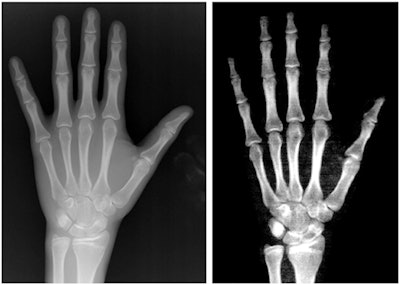

Standard bone age estimates to evaluate bone age in pediatric patients are qualitative and based on the doctor's recognition of maturation features on hand x-rays compared with a reference atlas. As an alternative, some researchers have suggested that DEXA imaging may be a valuable alternative, especially since it allows for a reduction in radiation dose in vulnerable pediatric patients, according to the authors.

The researchers culled images of 711 children and adolescents (307 female) aged 5 to 16 who underwent evaluations of the hand in two previous clinical trials. For all subjects, hand and wrist images for both techniques were obtained during the same day. For every hand and wrist reading, both x-ray and DEXA images were performed by two pediatric endocrinologists.

The authors hypothesized that the lower beam energy of DEXA implies a lower quality image compared to conventional x-ray imaging, and that this factor translated into a high probability of bone age overestimation in DEXA images in their study compared with x-rays.